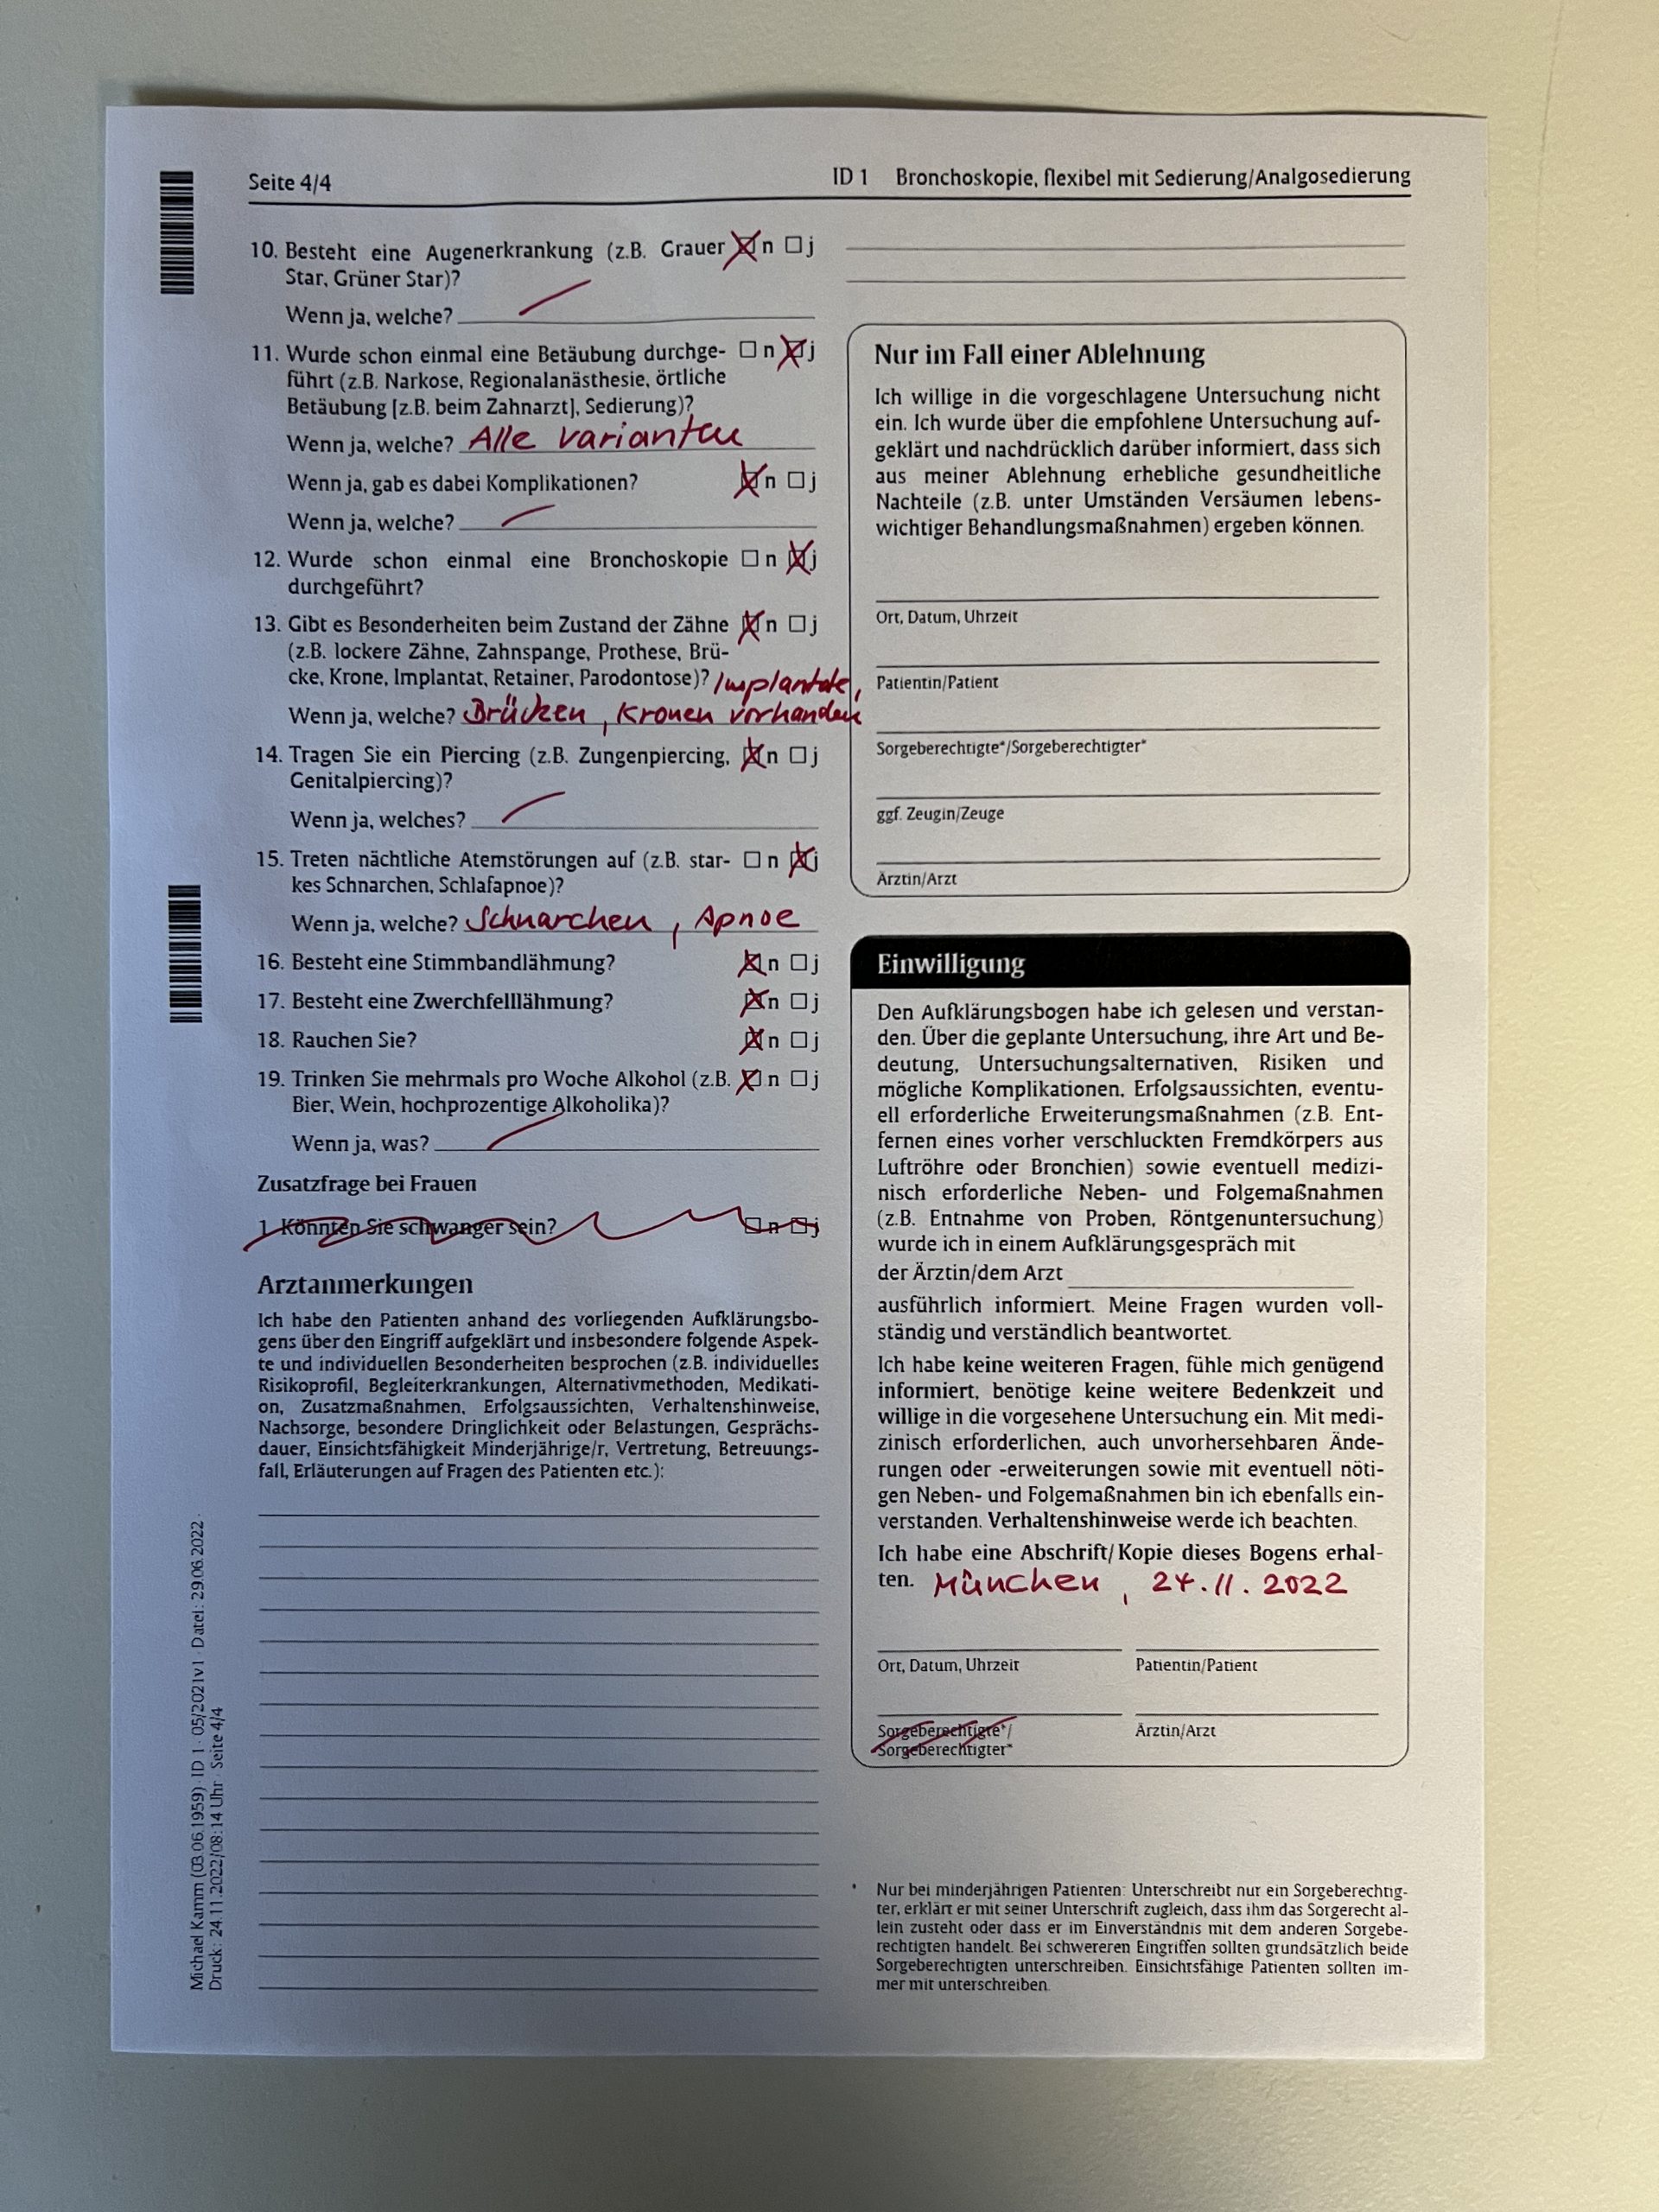

Ganz ohne Risiken ist der Eingriff nicht ... die erschreckende Liste der möglichen Problemfelder sollte man sich nicht zu oft durchlesen, sonst könnte man dazu neigen wieder Abstand von dem Vorhaben zu nehmen